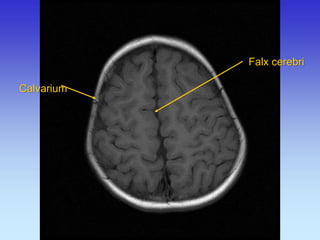

Falx cerebri

Calvarium